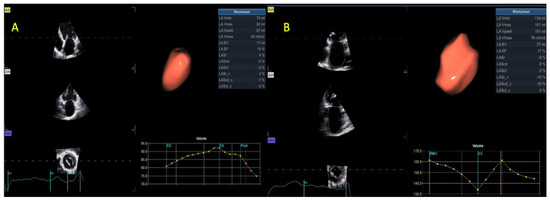

| 3D LAV max (mL) | 80 ± 22 | 107 ± 35 | <0.001 |

| 3D LAV max index (mL/m2) | 44 ± 13 | 55 ± 14 | 0.002 |

| 3D LAV min (mL) | 58 ± 25 | 89 ± 29 | <0.001 |

| 3D LAV min index (mL/m3) | 32 ± 14 | 44 ± 15 | 0.002 |

| 3D LA EF (%) | 30 ± 15 | 17 ± 6 | <0.001 |

| 3D RAV max (mL) | 57 ± 27 | 87 ± 43 | 0.001 |

| 3D RAV max index (mL/m2) | 31 ± 14 | 44 ± 21 | 0.006 |

| 3D RAV min (mL) | 40 ± 24 | 67 ± 35 | <0.001 |

| 3D RAV min index (mL/m2) | 22 ± 12 | 34 ± 19 | 0.005 |

| 3D RA EF (%) | 31 ± 12 | 23 ± 12 | 0.01 |